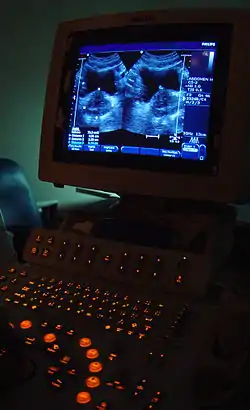

Medical imaging

Medical/biomedical imaging is a major segment of medical devices. This area deals with enabling clinicians to directly or indirectly "view" things not visible in plain sight (such as due to their size, and/or location). This can involve utilizing ultrasound, magnetism, UV, radiology, and other means.

Imaging technologies are often essential to medical diagnosis, and are typically the most complex equipment found in a hospital including: fluoroscopy, magnetic resonance imaging (MRI), nuclear medicine, positron emission tomography (PET), PET-CT scans, projection radiography such as X-rays and CT scans, tomography, ultrasound, optical microscopy, and electron microscopy.